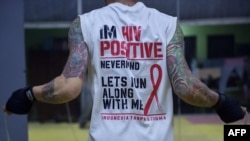

Peringatan Hari AIDS sedunia pada 1 Desember tahun ini mengangkat tema global “Biarkan Komunitas Memimpin.”

Menurut Program Gabungan Perserikatan Bangsa-Bangsa untuk HIV/AIDS (UNAIDS), dunia dapat mengakhir AIDS, dengan melibatkan komunitas secara signifikan. Organisasi masyarakat yang hidup dengan, berisiko, atau terdampak oleh HIV adalah garda terdepan dalam penanggulangan HIV.

Hingga September 2023, dari estimasi 515.455 orang dengan HIV (ODHIV), yang baru terindentifikasi sekitar 454 ribu orang atau 88 persen. Dari jumlah itu, 209 ribu ODHIV atau sekitar 40 persen di antaranya sedang mendapat pengobatan antiretrovilar (ARV). Untuk itu dibutuhkan dukungan komunitas agar semakin banyak ODHIV yang dapat mengakses pengobatan.

“Komunitas lah yang mungkin mempunyai akses yang lebih besar di dalam pendampingan kepada ODHIV dan bisa membantu mereka untuk bisa mengakses layanan terapi maupun layanan laboratorium,” tambahnya.